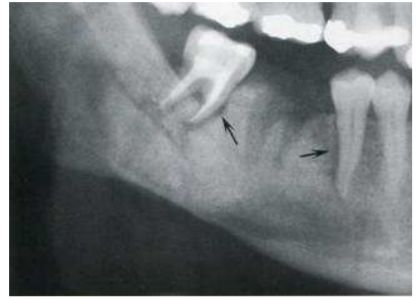

12.如下圖所示,下顎左側第三大臼齒依Pell and Gregory classification方法分類,下列何者正確? (A)class A (B)class 2 (C)class B (D)class 3

72.附圖X光片中,黑色箭頭所指為惡性細胞侵犯牙周韌帶所造成之影像,下列何種病變較不可能有此影像? (A)多發性骨髓瘤(multiple myeloma) (B)軟骨肉瘤(chondrosarcoma) (C)骨性肉瘤(osteogenic sarcoma) (D)纖維肉瘤(fibrosarcoma)